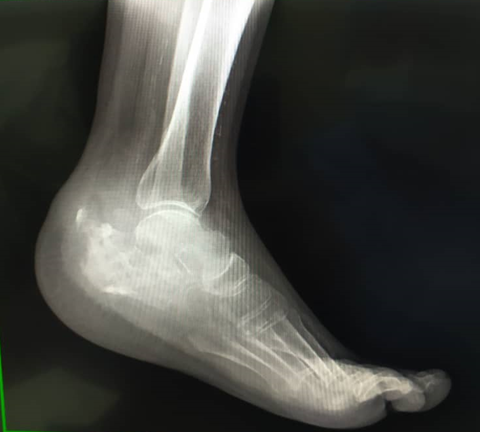

The image studies performed in a serial way, allow to observe the osteolytic process and the inflammatory response seen in those chronic cases. MRI, is especially useful in evaluating soft tissues, and the computed tomography, very much useful in evaluating bone destruction, worked together in these cases. It should be advice, the use of the bone scan, or PET-CT or virtual-PET, to discard polyarticular affectation. This entity is very often confused with other pathologies. Differential diagnosis has to be made with osteomyelitis, Paget’s disease, sarcomas and other pseudo tumoral lesions, which usually are the initial diagnosis, and TBC is a discard diagnosis. The adequate diagnosis is made late because of lack of pathognomonic findings (Figure 1 - 4).10

Figure 3 Lateral x-ray of the left foot. December 2020.

A needle biopsy (trucut) and culture of the sample is performed on the 11-18-2020, with results showing chronic granulomatous inflammation with multinucleated giant cells, focus of necrosis, an inflammation, probably due to infection, no discarding bony tuberculosis. On 12-07-2020, a positive response to PPD test (18 mm) is reported, and besides that the culture reports positive for Staphylococcus aureus, being diagnosed as: Bony tuberculosis of the left calcaneus bone, superinfected. Lab tests are performed not showing alterations, and on the chest, x-rays taken on 01-18-2021 depicted left pleural effusion without any respiratory symptoms.